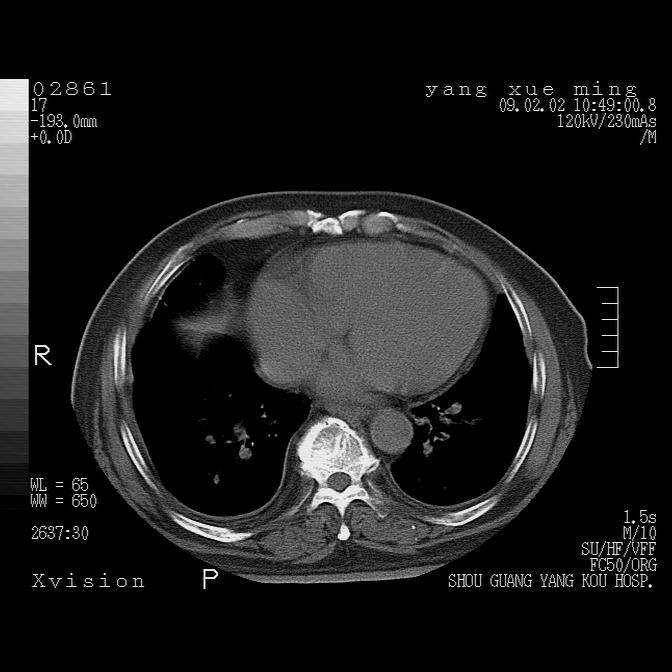

以下是引用lkc8963在2009-2-3 20:11:00的发言:[br]1)右上肺陈旧病灶。2)右下肺团块及团片影,影像表现符合感染。3)左心增大,左冠脉钙化,符合冠心病。4)双侧肺门扩大,以左侧为著,肺动脉干略粗,左上肺局限性气肿,为谨慎起见,需除肿瘤,建议增强。

以下是引用zbp537在2009-2-3 19:08:00的发言:[br]我诊断为肺泡性肺水肿。[br]诊断依据:[br]1、心影普遍增大,肺血管增粗,并见絮状高密度影,肺门改变显著。[br]2、临床上表现胸闷咳嗽,无发烧,不是一个典型的肺部感染的病史。